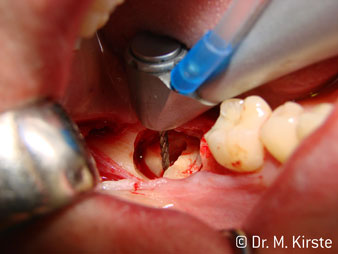

45° ъгъл на наконечника е специално избран поради неговата широка гама от предимства. Колеги, които работят хирургия, и за които този наконечник е главно създаден, скоро ще оценят възможността за ефективна работа в силно ограничени пространства. При екстрахиране на мъдреци, в частност (фиг. 2), няма нужда от голямо разширяване на меката тъкан в областта на бузата (фиг. 3). Дизайнът на главата на наконечника, в съчетание с лекото завъртане на главата по време на препарация, позволява бърза и безопасна работа в ретромоларната област.

Специалният дизайн на лагерите в главата на наконечника гарантира безшумен ход на борера; това прави впечатляващо атравматичен разрез при отделянето на зъба и корена (фиг. 4-9).

45° обратен наконечник е много удобен в ръка. Забелязвате почти веднага, че работната глава имитира ъгъла на вашия показалец и желаното движение просто се прехвърля няколко въображаеми сантиметра паралелно на върха. (Фиг. 1)”

Фиг. 1